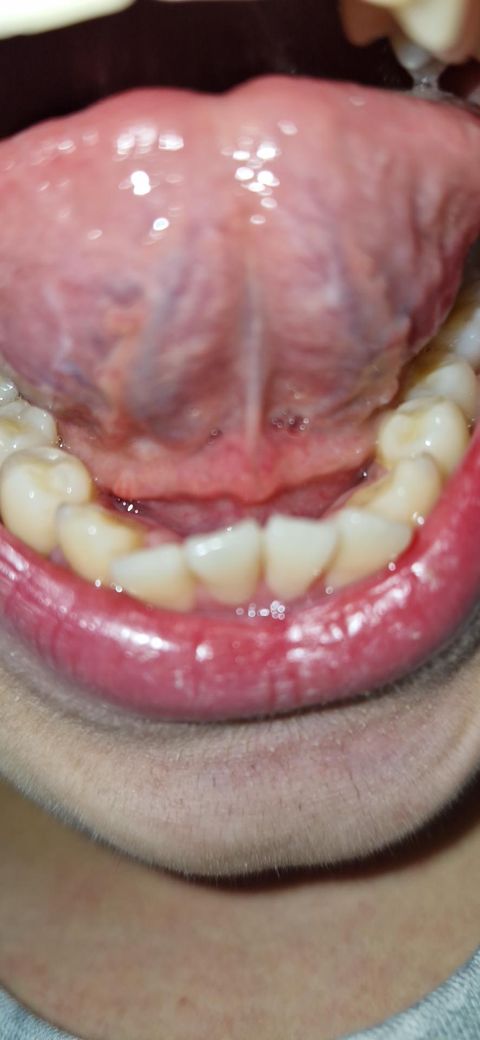

혀 밑에 이상한 살점? 같은게 있어요. 이쪽이 아프거나 하지는 않는데 뭔가 부어있는 것 같아요. 정말 부은건가요? 원인은 뭐가있나요?

그리고 앞니 잇몸과 혀 아래 사이 하얀색깔 점박이 같은게 있는데 이것도 문제있는건가요?